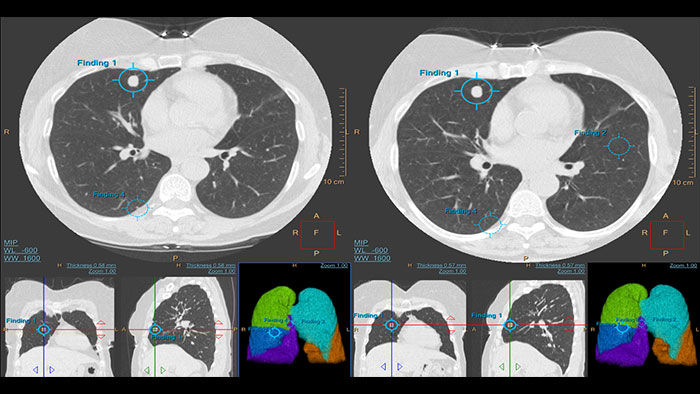

For diagnostic use and low-dose CT lung cancer screening

An advanced imaging package for the segmentation, quantification and follow-up of physician-indicated lung nodules, that can be used in both diagnostic and screening evaluations, supporting Low Dose CT Lung Cancer Screening.*

Rely on an artificial second reader Computer-aided detection system for chest multi-slice CT exams

Artificial second reader to support in detection of lesions or nodules which may have been missed.

- detect potentially actionable lung nodules – not just round objects or ROIs - correlate 2D, 3D, and lung maps - register current and prior nodules - calculate nodule changes